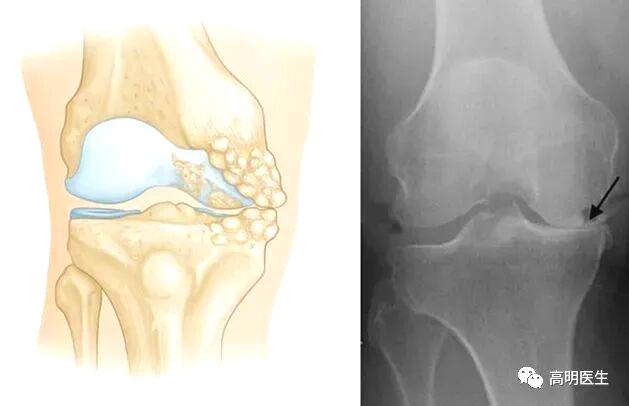

关节炎不是冻出来的

首先明确一点:寒冷刺激不是关节炎的病因。关节炎是一类疾病的统称,包括骨关节炎、类风湿性关节炎、痛风性关节炎等,其中最为常见的是骨性关节炎。膝关节骨性关节炎,是一种膝关节的退行性疾病,主要临床表现为膝关节疼痛、肿胀及活动受限,主要病理表现为膝关节软骨的纤维化、磨损、剥脱等伴发滑膜充血水肿及骨赘增生等。据不完全统计,我国 60 岁以上人群发病率为 50%,75 岁以上人群高达 80%,全国大概有 1.2 亿人遭受膝关节骨性关节炎疼痛的困扰。研究显示膝关节骨性关节炎患者中,近 20%会伴随焦虑及抑郁症状,是导致全世界中老年人生活质量降低和经济负担加重的重要原因。它们的成因各不相同,但都与寒冷无直接因果关系。

· 骨关节炎:最常见的类型,主要由关节软骨的退化引起。年龄增长、肥胖、过度使用关节、遗传因素等才是主要发病原因。

关节就像汽车轮胎,也有“使用寿命”。随着年龄增长,关节软骨逐渐磨损,弹性下降,最终出现骨赘(俗称“骨刺”),这就是骨关节炎的过程 。 只不过有些人的关节耐磨,有些人的不耐磨罢了。不仅人类,几乎所有脊椎动物都会得骨关节炎,但是对于一些关节负荷极小的动物(如蝙蝠、树懒等)发病率极低。这也说明骨关节炎是关节对磨损的自然反应。